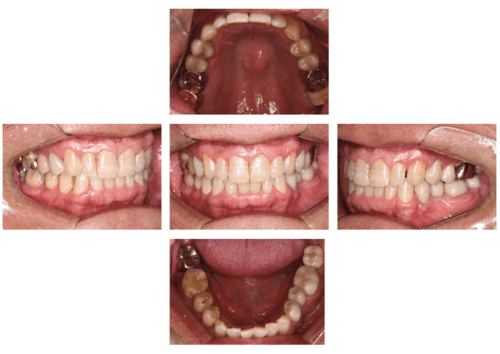

症例写真-1

- Befor

- After

症例写真-2

- 途中経過

| 年齢 | 50代・男性 |

| 主訴 | 右下歯が疼く |

| 治療内容 | ・右下6番インプラント ※1:FGG(遊離歯肉移植術)とは、足りない歯ぐきを上顎から上皮を切り取り移植する外科手術 |

| 治療費 | 合計:902,000円(税込) ■内訳 |

| 治療期間 | 9ヵ月 |

| 治療方針 | 右下の当該歯は歯根破折により保存不可能と診断しました。歯周疾患も伴っていたため抜歯後に骨吸収※1が大きく起こることが予測できました。チタンメッシュ併用骨再生誘導法(GBR※2)を選択しインプラント埋入と同時に行い自然な歯槽骨のラインを再現しました。またGBRを行う際にインプラント辺縁の付着歯肉の減少が起こる為、遊離歯肉移植術(FGG※3)を行い清掃性を考慮した形態に仕上げました。 ■治療方針の解説 治療した右下の歯をレントゲンで撮影したところ根本の部分に黒く写る箇所があり「根尖性慢性周囲炎※1」と診断。また歯周病も進行していました。 ※1 骨吸収・・・歯槽骨という歯を支える骨がなくなっていくこと |

| 担当者所見 | 主訴の右下だけでなく歯茎の腫れ、発赤があり不良補綴や不良充填など他にも治療箇所が多数ありました。プラークコントロールが不良であった為まずはブラッシング指導を行いセルフケアの重要性を理解していただくところからスタートしました。 右下6番の歯はインプラント治療を行なった結果審美的にも機能的にも患者様の満足を得ることができました。骨造成と歯肉移植も行なった為インプラントを支える十分な歯周組織の獲得ができたと思っております。 |